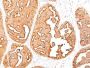

This MAb recognizes full-length MUC1 in a glycosylation-independent manner and can bind to the fully glycosylated protein. The dominant epitope of this MAb is APDTR in the VNTR region. It reacts with the core peptide of the MUC1 protein, which is a member of a family of mucin glycoproteins that are characterized by high carbohydrate content, O-linked oligosaccharides, high molecular weight (>200 kDa) and an amino acid composition rich in serine, threonine, proline and glycine. The core protein contains a domain of 20 amino-acid tandem repeats that functions as multiple epitopes for the MAb. Incomplete glycosylation of some tumor-associated mucins may lead to variable unmasking of the multiple peptide epitopes leading to the observed differences in staining intensity between normal and malignant tissues. This MAb reacts with both normal and malignant epithelia of various tissues including breast and colon.Primary antibodies are available purified, or with a selection of fluorescent CF® Dyes and other labels. CF® Dyes offer exceptional brightness and photostability. Note: Conjugates of blue fluorescent dyes like CF®405S and CF®405M are not recommended for detecting low abundance targets, because blue dyes have lower fluorescence and can give higher non-specific background than other dye colors.

MCF-7 or MDA-231 cells. Breast, colon, ovarian, endometrial carcinoma.

Immunohistology formalin-paraffin 0.25-0.5 ug/mL|Staining of formalin-fixed tissues requires boiling tissue sections in 10 mM citrate buffer, pH 6.0, for 10-20 min followed by cooling at RT for 20 minutes|Flow Cytometry 0.5-1 ug/million cells/0.1 mL|Immunofluorescence 1-2 ug/mL|Optimal dilution for a specific application should be determined by user